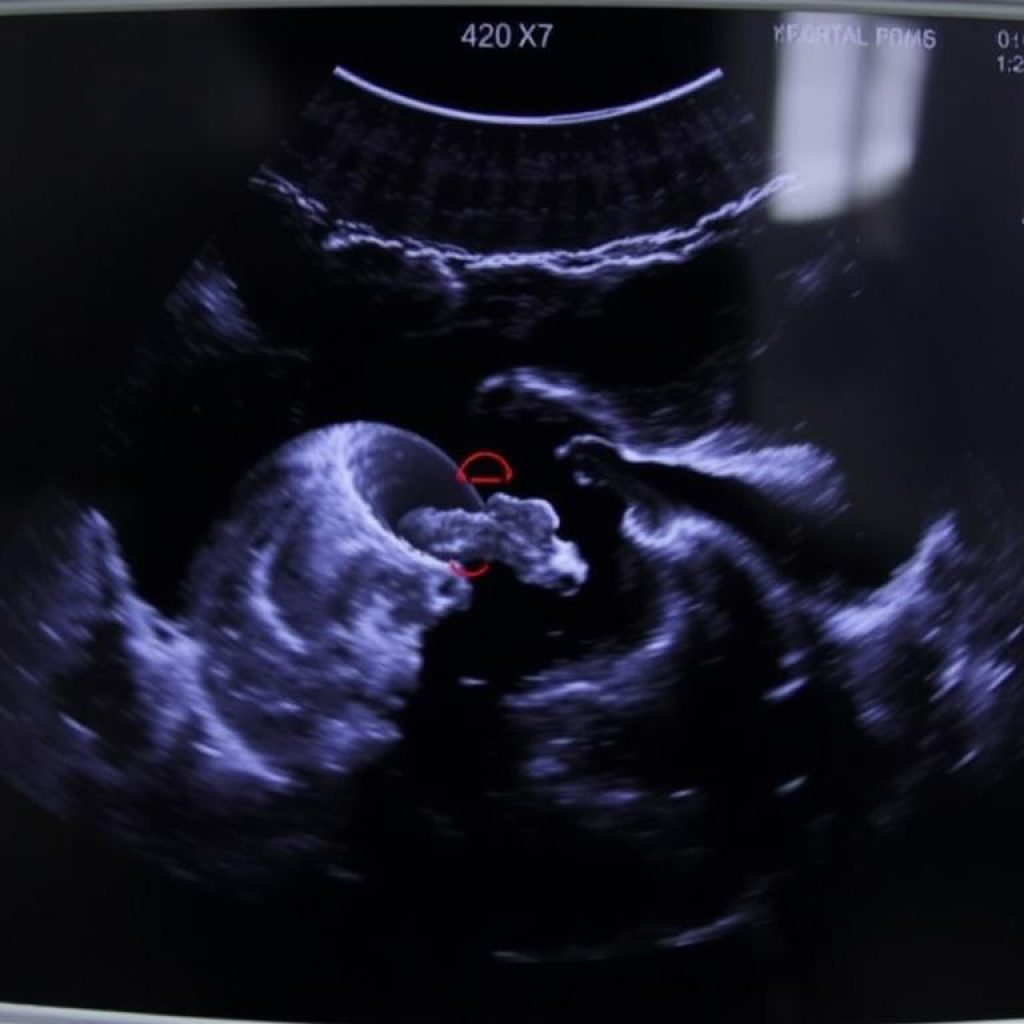

Ultrasonografi (USG)

Ultrasonografi (USG) adalah metode diagnostik yang paling umum digunakan untuk mendeteksi Plasenta Previa. USG dapat menunjukkan lokasi plasenta dan apakah plasenta tersebut menutupi saluran lahir. Ada dua jenis USG yang dapat digunakan:

- USG transabdominal: Digunakan untuk melihat plasenta dan janin secara keseluruhan.

- USG transvaginal: Memberikan gambaran yang lebih detail tentang hubungan antara plasenta dan serviks.

Penelitian terbaru telah mengidentifikasi beberapa pendekatan baru dalam penanganan Plasenta Previa. Salah satu temuan signifikan adalah penggunaan teknik ultrasonografi yang lebih canggih untuk memantau kondisi plasenta secara lebih akurat.

Menurut sebuah studi yang dipublikasikan dalam jurnal kedokteran terkemuka, “Penggunaan ultrasonografi 3D dan 4D dapat membantu dalam diagnosis yang lebih tepat dan perencanaan perawatan yang lebih baik.”